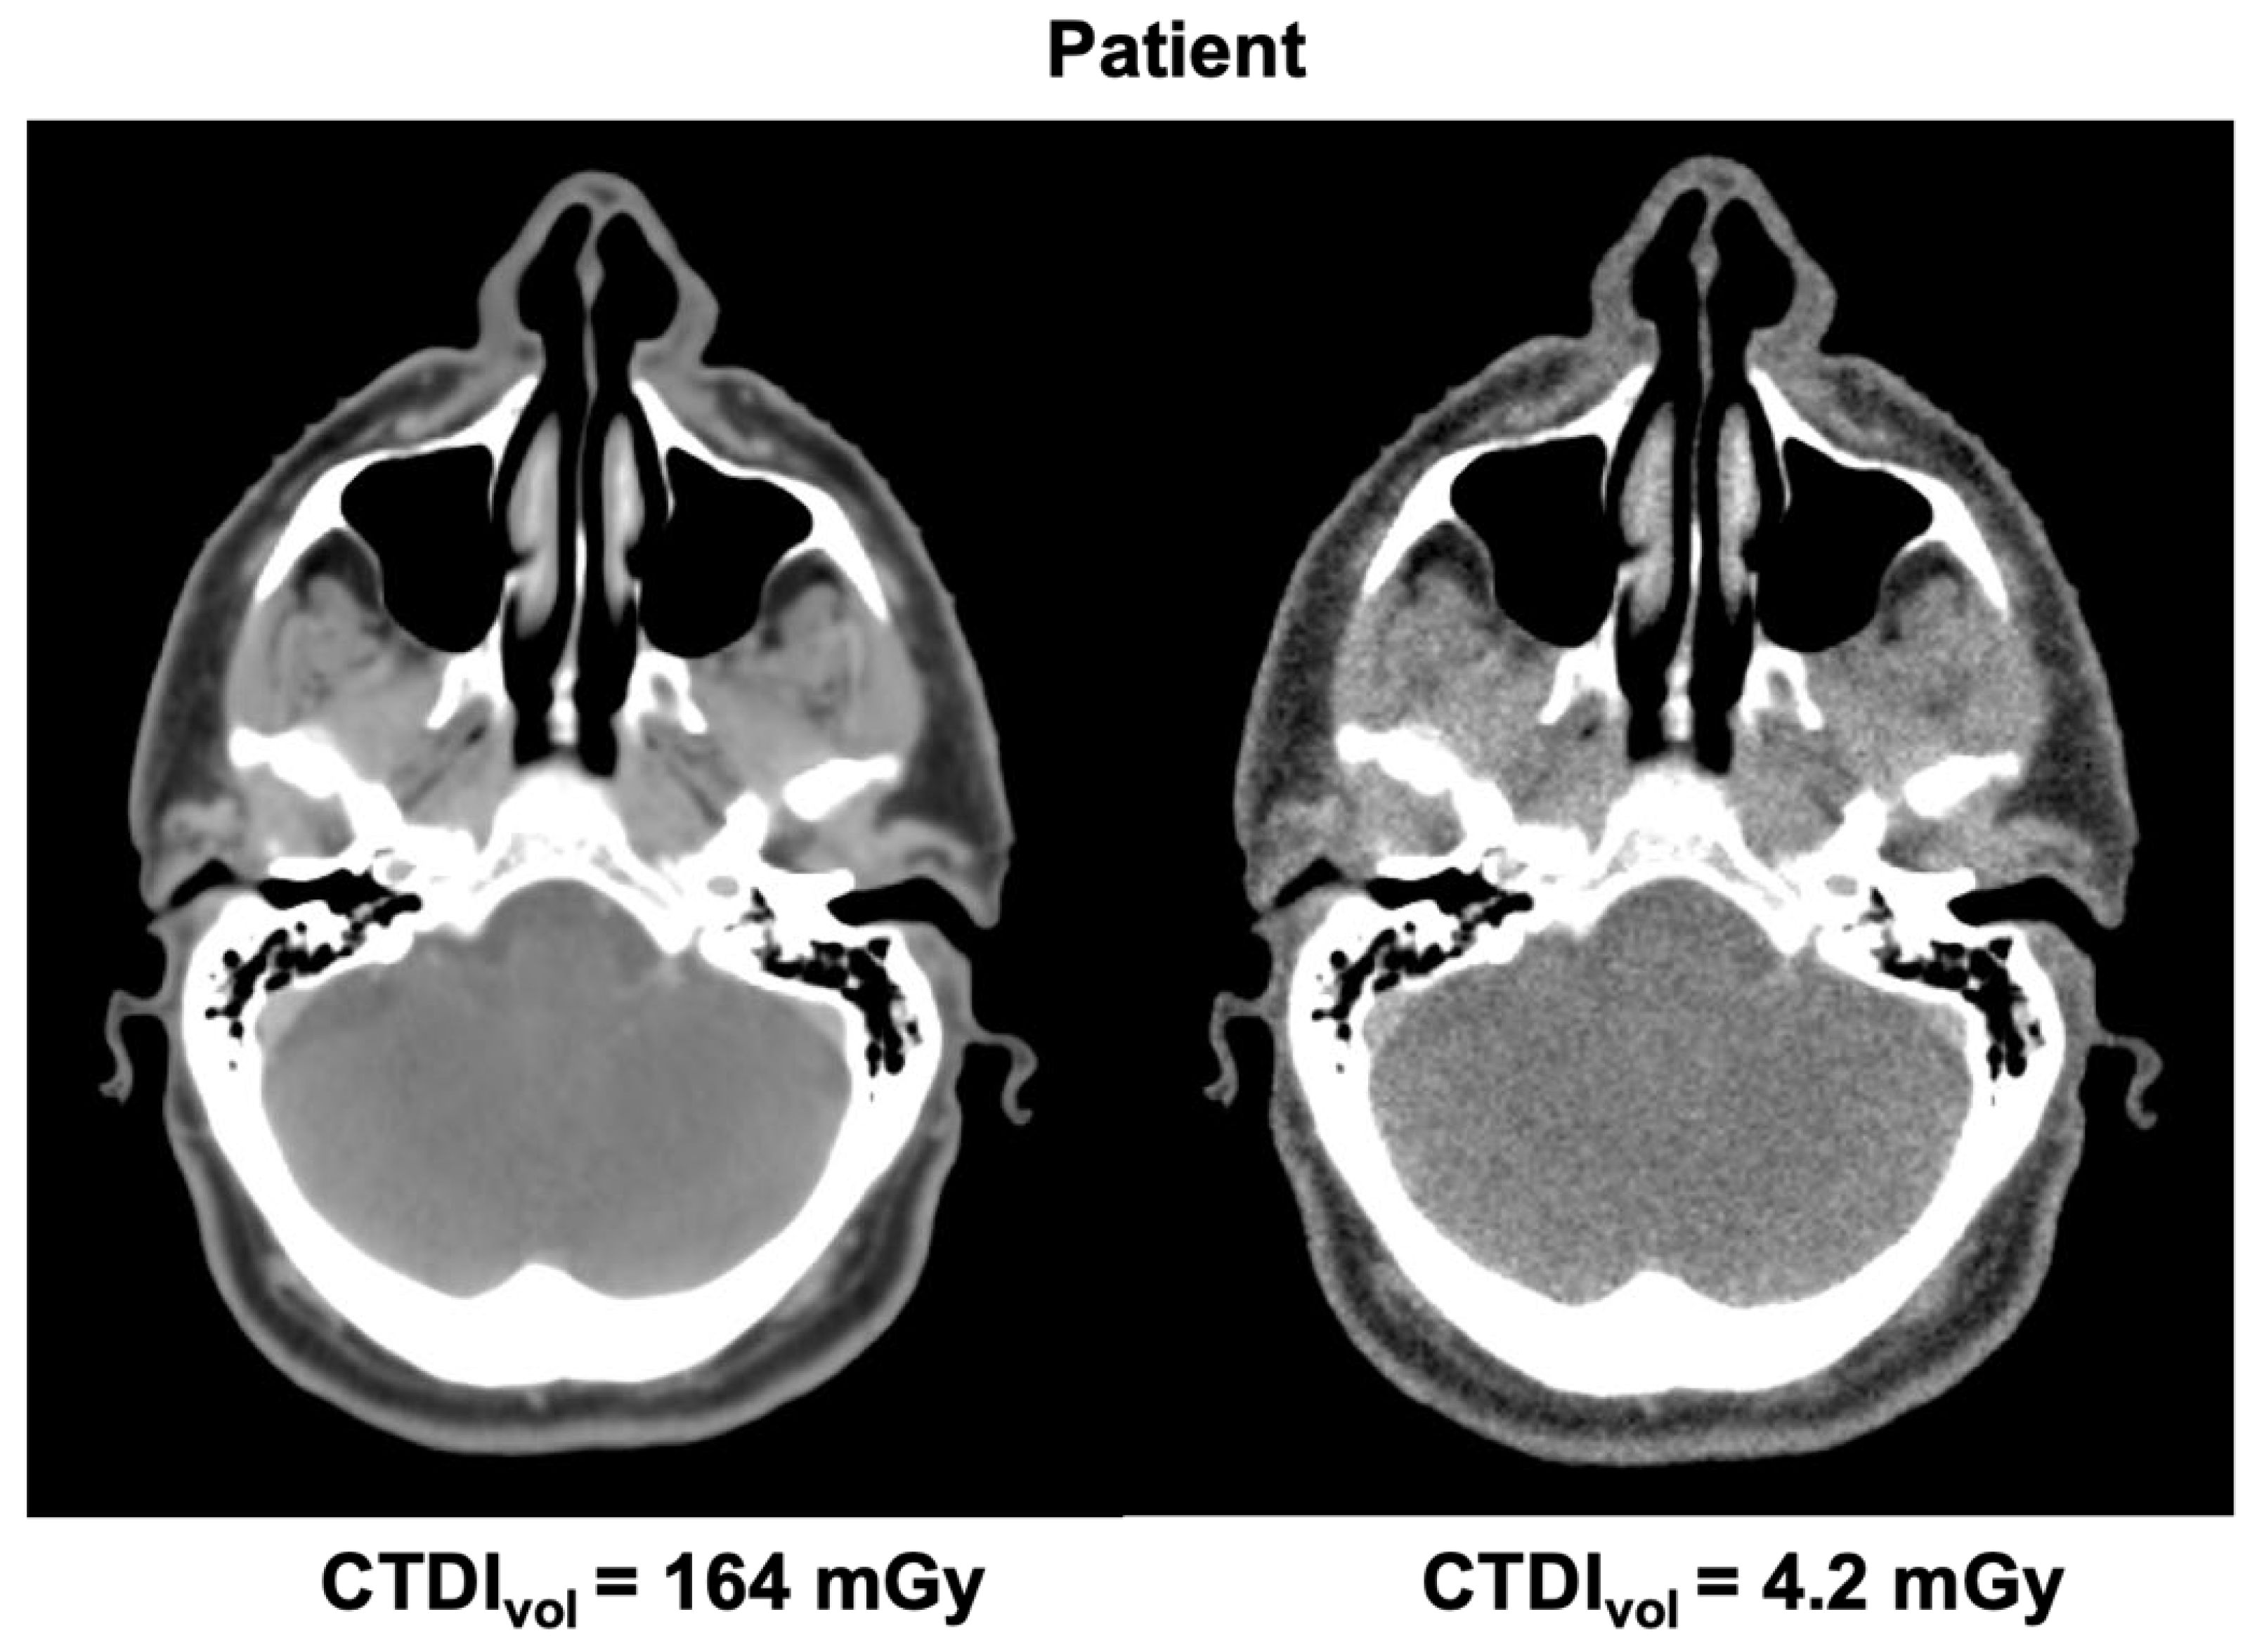

In order to produce synthetic low-dose vCT images for each patient, each voxel in the original vCT was assigned with a CT number randomly chosen from a Gaussian distribution with the mean and sigma taken from the lookup table. Since only a subset of voxels in phantom images were analyzed to limit the computing time (11 central sagittal slices), we performed quality assurance of the synthetic low-dose vCTs with the criterion of at least 99.9% voxels being assigned with a new CT number. Figure 4 shows a pair of vCT images for one patient: original (standard protocol) and synthetic corresponding to the lowest dose (CTDIvol = 4.2 mGy).

Figure 4.

Pair of vCT images of a patient: standard protocol (left) and low-dose protocol (right).